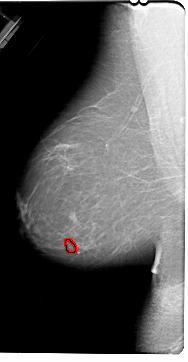

A_1830_1.LEFT_CC

LEFT_CC LINES 6076 PIXELS_PER_LINE 3826 BITS_PER_PIXEL 12 RESOLUTION 43.5 OVERLAY

FILE: A_1830_1.LEFT_CC.OVERLAY

TOTAL_ABNORMALITIES 1

ABNORMALITY 1

LESION_TYPE MASS SHAPE OVAL MARGINS ILL_DEFINED

ASSESSMENT 4

SUBTLETY 2

PATHOLOGY BENIGN

TOTAL_OUTLINES 1

BOUNDARY